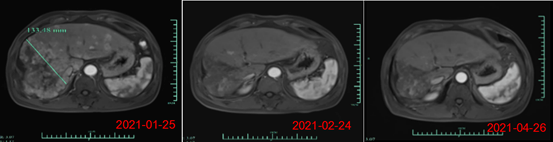

其中,受试者007的PR缓解时间超过6个月,肿瘤体积减少超过80%。截止日前该患者的缓解周期已超过8个月,仍在持续随访中。另一名疗效显著的受试者012是一位弥漫型、巨块型晚期的肝癌患者,曾接受过12次以上的TACE治疗,在放疗及靶向治疗无效后加入本研究。

回输28天后MRI结果显示最大肿瘤直径从133mm减少至9mm,缩小超过93%。目前,该受试者在回输3个月后评估,MRI扫描结果显示此肿瘤几乎消失。相应地,回输28天后其AFP(甲胎蛋白,诊断原发性肝癌特异性的肿瘤标志物)水平从>80000降至1148.9ng/ml,回输3个月后降至746.7ng/ml(其正常值是在0-40ng/ml以内),展示了Ori-CAR-001在晚期肝癌治疗的显著有效性。